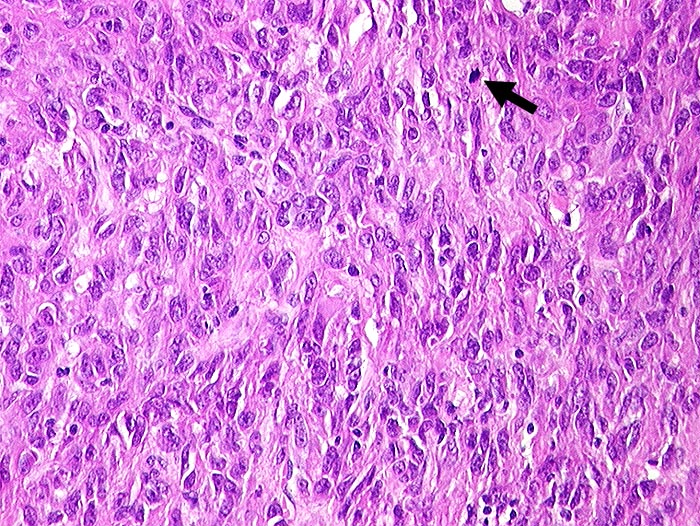

Es wird vorgeschlagen die gastrointestinalen Stromatumoren, welche CD117 positiv reagieren als GIPACT zu benennen. Die CD 117 positiven Tumoren scheinen von interstitiellen Schrittmacher Zellen von Cajal abzustammen.

Gastrointestinal pacemaker cell tumor... S. Schmid, W. Wegmann. Virchows Archive 2000. 436: 234-242.